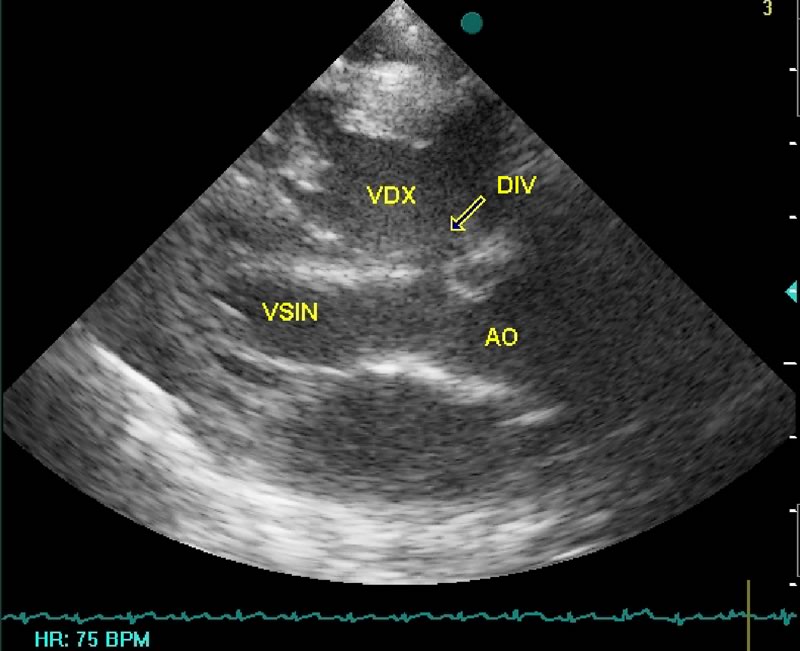

L'ecocardiografia evidenzia la presenza di un difetto interventricolare sottoaortico tra aorta e tricuspide con diametro superiore al 50% dell'aorta (Fig. 2), senza alcuna copertura aneurismatica, con sovraccarico di volume del ventricolo e dell'atrio sinistro; al color doppler ampio jet sinistro-destro a bassa velocità suggestiva per elevata pressione in ventricolo destro (Fig. 3).